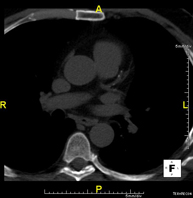

- Thoracic aorta CT angiography

Diagnostic test to examine the thoracic aorta (main artery of the thorax) using CT (Computed Tomography) equipment. This technique provides high-definition anatomical images. In most cases, the use of iodinated contrast is necessary. The use of MDCT (Multidetector Computed Tomography) shortens scanning time, reduces radiation dose and improves image quality. The multiple detectors used in certain studies enable imaging to be synchronised with the heartbeat, a technique used to study the aortic valve and aortic root (the first few centimetres), where the heartbeat tends to distort images due to movement.